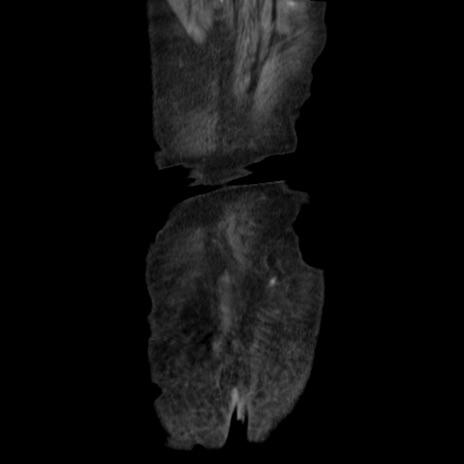

矢状断像

【症例】80歳代 女性

【主訴】腹部膨満感

【現病歴】他院にて肝硬変にてフォロー中。1週間前から便秘、腹部膨満感、臍部腫瘤あり受診となる。

【既往歴】肝硬変

【身体所見】腹部膨隆あり、皮膚変化なし、疼痛なし。

【データ】WBC 4600、CRP 0.25